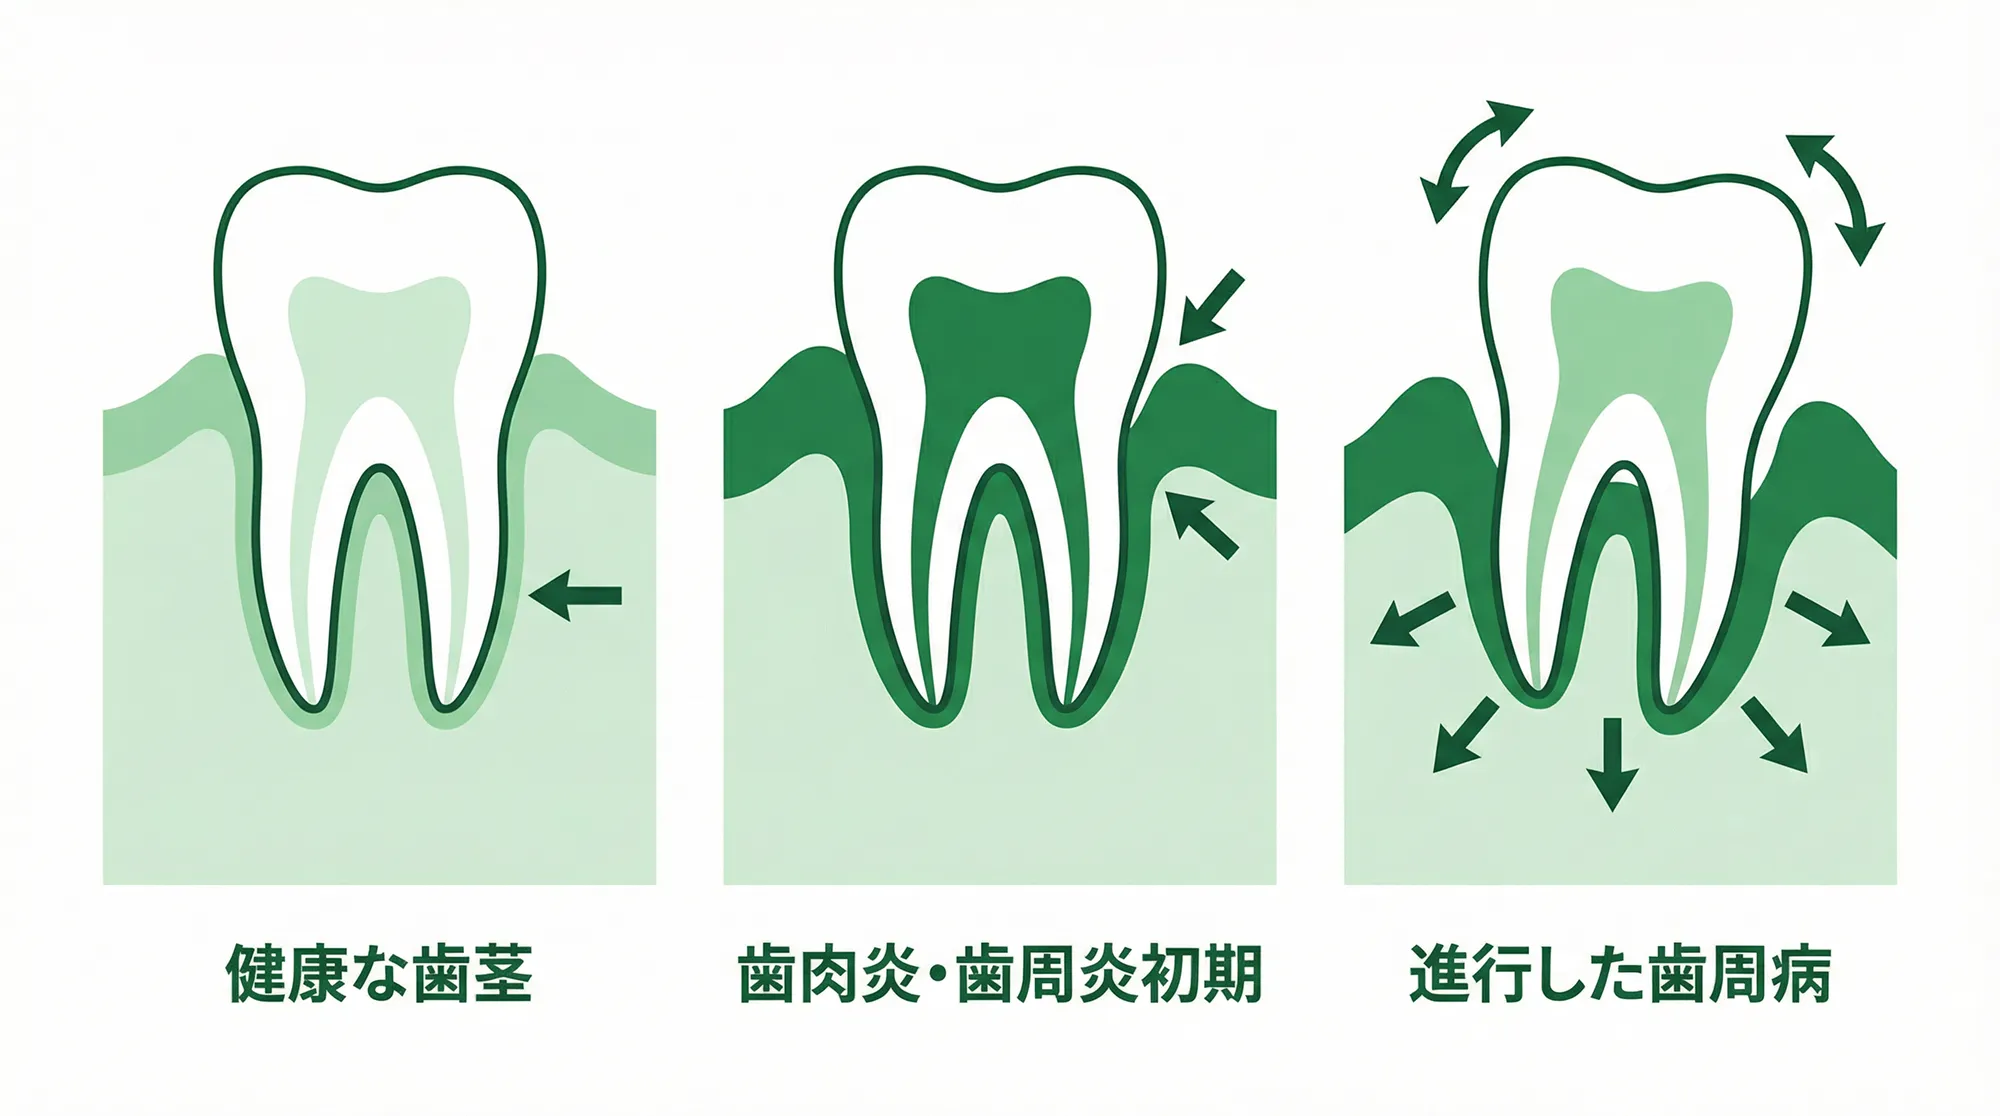

歯周病が全体に進行しており、グラグラの状態

歯周病で歯全体がグラグラしている

重度の歯周病で歯全体がグラグラしている場合、従来は抜歯後に骨が回復するのを待ってからインプラント治療を始める必要がありました。そのため、治療完了まで長い期間がかかってしまうことが課題でした。

オールオン4・6なら、抜歯と同時にインプラントを埋入し、その日のうちに仮歯を装着することができます。治療期間を大幅に短縮できるだけでなく、「歯がない期間」を最小限に抑えることができます。

オールオン4・6治療が難しい方

オールオン4・6は多くの方に適した治療法ですが、以下のような場合は治療が難しいことがあります。

顎の骨の「量」や「密度」が著しく低い状態の方